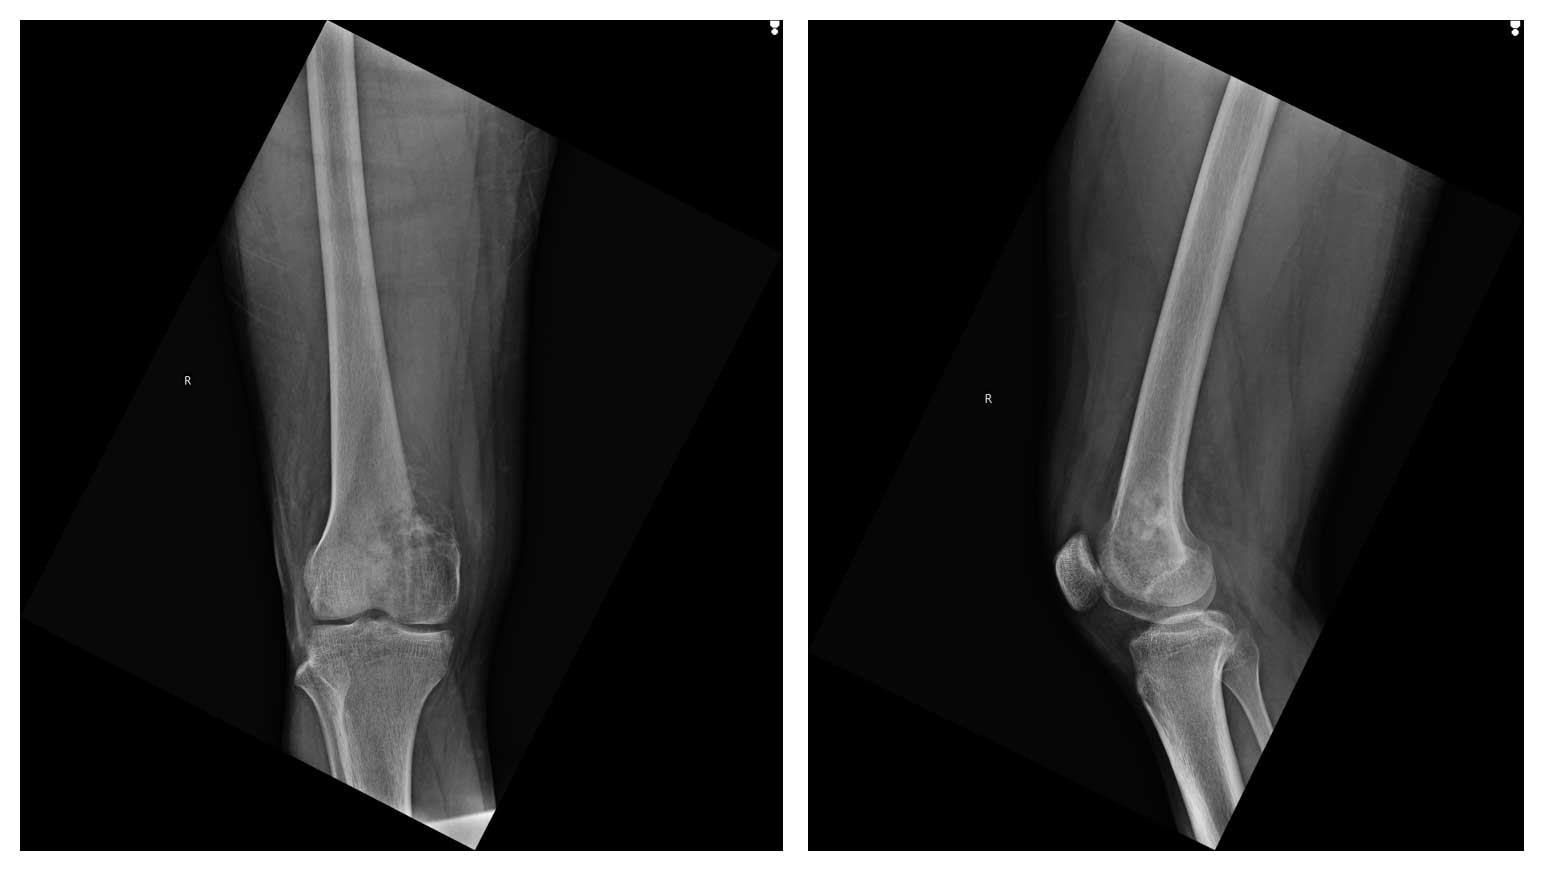

Ameliyat Öncesi: Röntgende distal femur medialde düzensizlik ve harabiyet görülmekte.